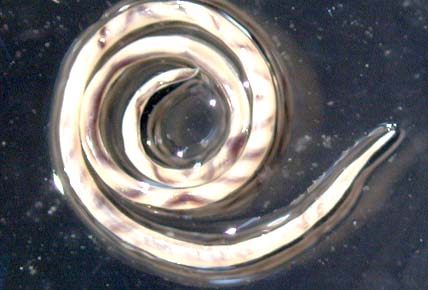

Nhiễm trùng G. spinigerum tại các vùng lưu hành bệnh ở Đông Nam Á, đặc biệt tại Thái Lan. Tỷ lệ mắc đang gia tăng ở Mexico và Trunghay Nam Mỹ. Vật chủ chính của các loài Gnathostoma là chó và mèo. Sau khi nuốt phải ấu trùng giai đoạn 3, các giun sẽ trưởng thành trong dạ dày của vật chủ và trứng sẽ được đào thải qua phân. Các ấu trùng đẻ ra có thể phát triển thành ấu trùng giai đoạn 2 khi chúng bị ăn phải các nhuyễn thể thuộc giống Cyclops. Các loài nhuyễn thể này rồi thì bị ăn bởi các vật chủ “paratenic hosts”, như cá, ếch, heo, rắn, gà và lươn. Giun trưởng thành sang giai đoạn ba khi chúng di chuyển vào trong mô cơ vật chủ và đóng kén tại đó. Nhiễm trùng có thể bỏ qua giai đoạn giữa các vật chủ “paratenic hosts”, gồm có con người, khi cơ nhiễm trùng bị nuốt phải. Con người bị nhiễm thông qua ăn các vật chủ “paratenic hosts” còn sống hay nấu chưa chín hoặc hiếm hơn thông qua ấu trùng xuyên trực tiếp vào da.

Chu kỳ của loài giun này gồm thể trưởng thành sống và đẻ trứng trong động mạch phổi của các loài gặm nhấm. Các loài Angiostrongylus sinh sản khi trứng đẻ ra và ấu trùng di chuyển vào trong hầu, được nuốt bởi các loài gặm nhấm và ấu trùng đi qua phân. Ấu trùng trở thành ấu trùng giai đoạn 2 và 3 khi chúng được nuốt hay xuyên qua một loài nhuyễn thể nào đó. Người mắc phải nhiễm trùng khi họ ăn các vật chủ trung gian này hoặc một số các vật chủ ‘paratenic host” khác như cua, ếch, tôm hồng hoặc ăn các rau sống chứa các chất từ các vật trung gian hay vật chủ paratenic (vỏ hay chất tiết). Rồi thì ấu trùng đi vào hệ thống tuần hoàn sau khi chúng đi qua đường tiêu hóa và di chuyển tới hệ thần kinh trung ương, ở đó chúng trưởng thành và gây bệnh trên các vật chủ không phải là chuột.

Kết luận: Nhiễm trùng giun sán đang nổi gây EM như bệnh ấu trùng giun đầu gai và giun mạch, các bệnh này có thể phòng bệnh thông qua giáo dục sức khỏe, thay đổi hành vi ăn uống và chế biến thức ăn hợp lý.